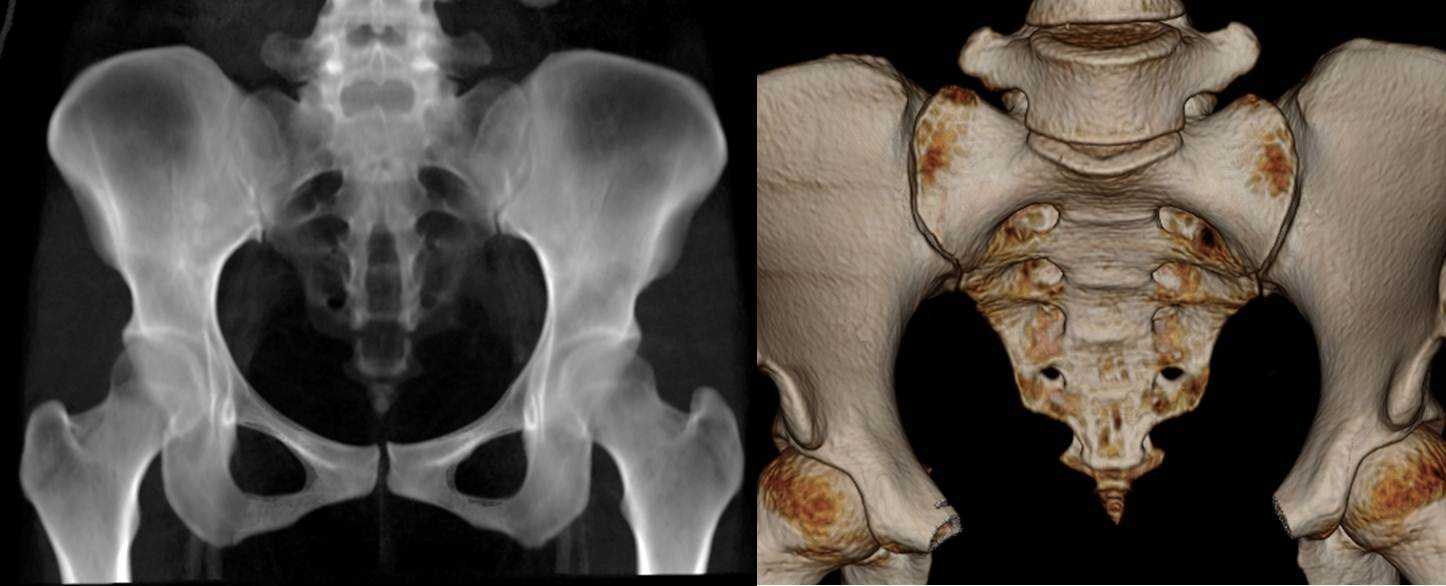

Рентгеновские снимки крестцово-копчикового отдела позвоночника